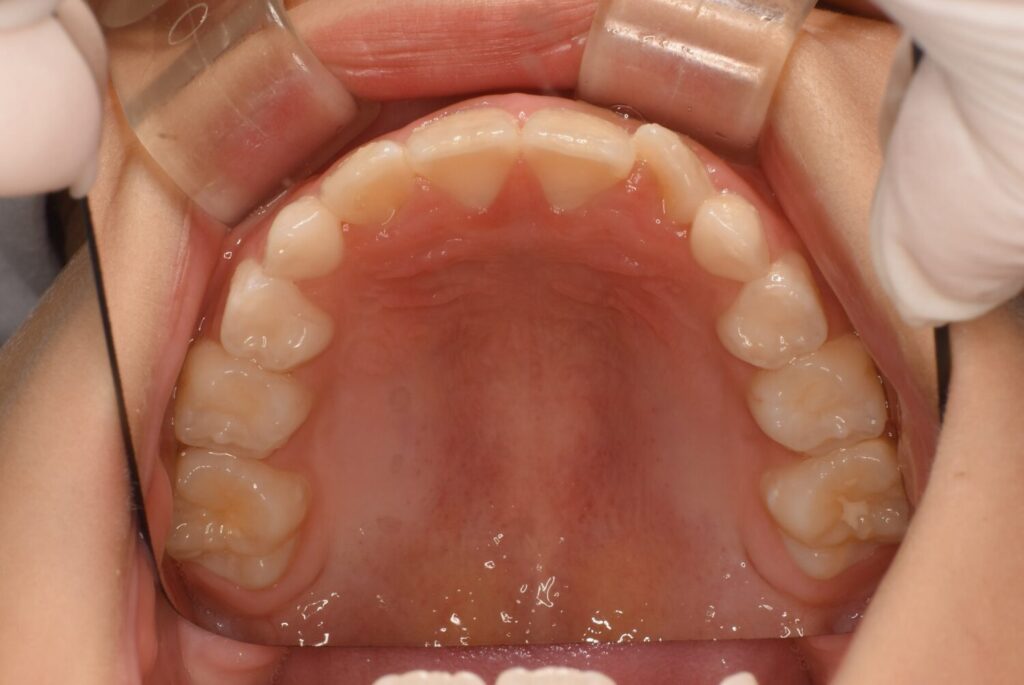

上の歯並びの変化

上の歯並びも3ヶ月後に見ると左の前から2番目の歯が綺麗に入っています。

ですが反対側の歯がまだ入りません。

でも確実に顎は大きくなってきています!